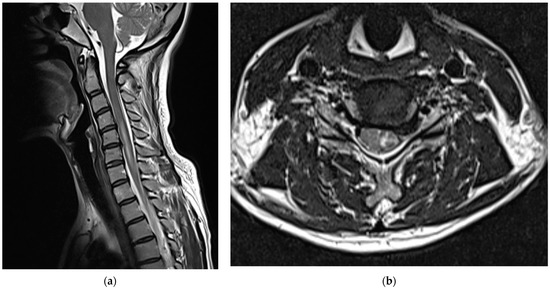

Before visiting our hospital, a 35-year-old woman with no specific medical history visited a spine hospital complaining of posterior neck pain radiating to the left upper arm. These symptoms appeared 6 months before she was admitted at the spinal hospital and had worsened to a Visual Analog Scale (VAS) score of 6 at the time of admission. No motor weakness or sensory changes were observed upon physical examination at the time of admission. However, numbness was observed in the left arm during the Spurling test. Magnetic resonance imaging (MRI) of the cervical spine showed a herniated intervertebral disc at the C5/6 level and left C6 nerve impingement due to left foraminal extrusion (Figure 1).

Figure 1.

Cervical spine magnetic resonance images obtained before the procedure. A herniated intervertebral disc at the C5/6 level and left C6 nerve impingement due to a left foraminal extrusion are observable on the (a) T2-weighted sagittal image and (b) T2-weighted axial image of the C5/6 level.